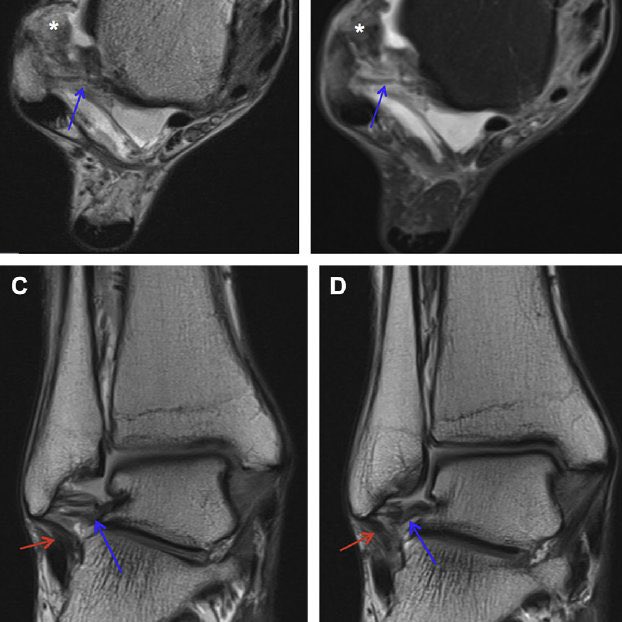

خلع في الوتر الشظوي وهو ما قد يتسبب في إلتهاب مزمن أو قطع

قطع مزمن في الوتر الكاحلي الشظوي بسبب الإصابات المتكررة عليه